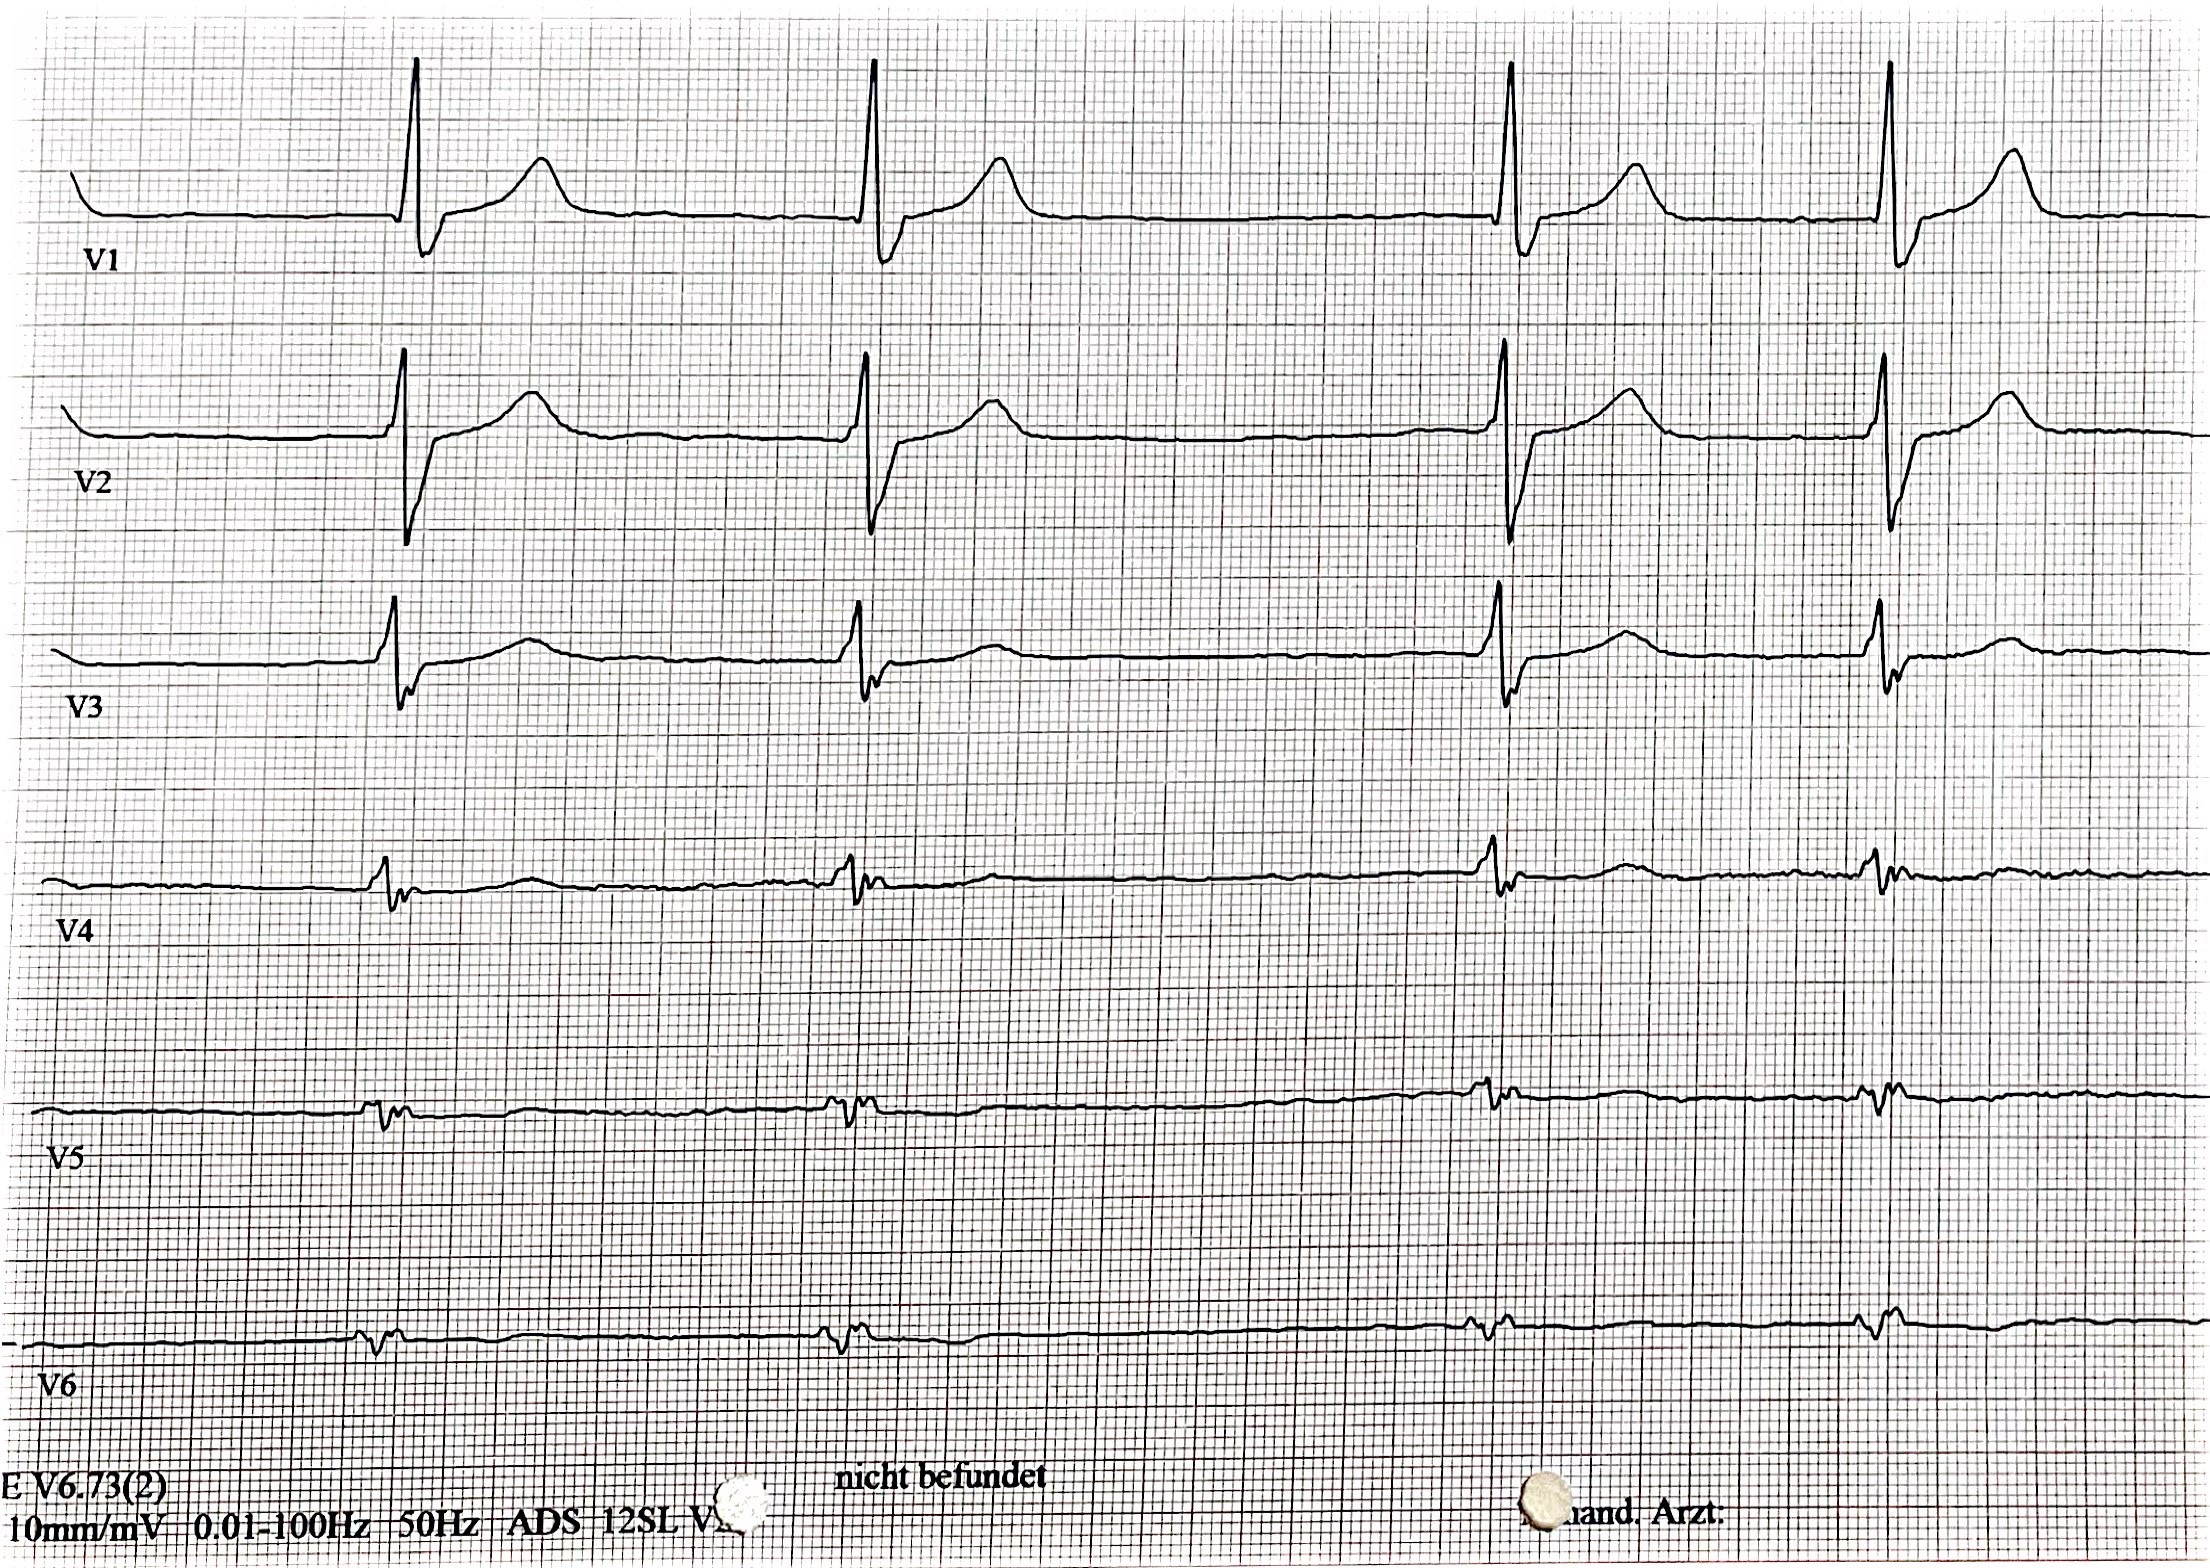

Ein 45-jähriger Patient wurde zur elektiven Kryoballonablation bei persistierendem Vorhofflimmern (EHRA IIa, CHA₂DS₂-VA-Score: 1) aufgenommen. Klinisch zeigte sich im EKG ein überdrehter Rechtstyp (siehe Abb. 1) als Hinweis auf Dextrokardie. Die präinterventionelle CT-Diagnostik (siehe Abb. 2-4) bestätigte die rechtsseitige Herzlage ohne begleitenden Situs inversus. Diese Bildgebung war essenziell für die prä-interventionelle Planung der PVI: Die transseptale Punktion und die Navigation der Katheter erfolgten unter transösophagealer Echokardiographie und angepassten Durchleuchtungsebenen (siehe Abb. 5) mit Beachtung der veränderten räumlichen Orientierung auf Grundlage der CT Diagnostik. Besonders wichtig war dabei die systematische Anpassung der Durchleuchtungs-Ebenen um eine adäquate Darstellung der Pulmonalvenen während der Prozedur zu gewährleisten. Die Kryoablation aller vier Pulmonalvenen erfolgte erfolgreich und komplikationsfrei.

Abb. 1: EKG